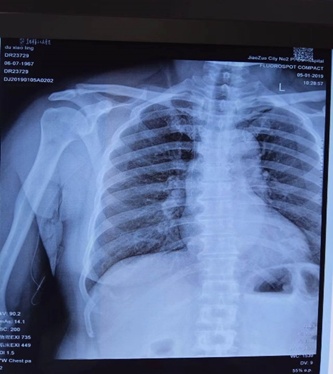

二、如何定位?

通过胸部正位片确定导管尖端位置。理想的位置应该是导管尖端位于上腔静脉中下1/3或上腔静脉和右心房交界处。